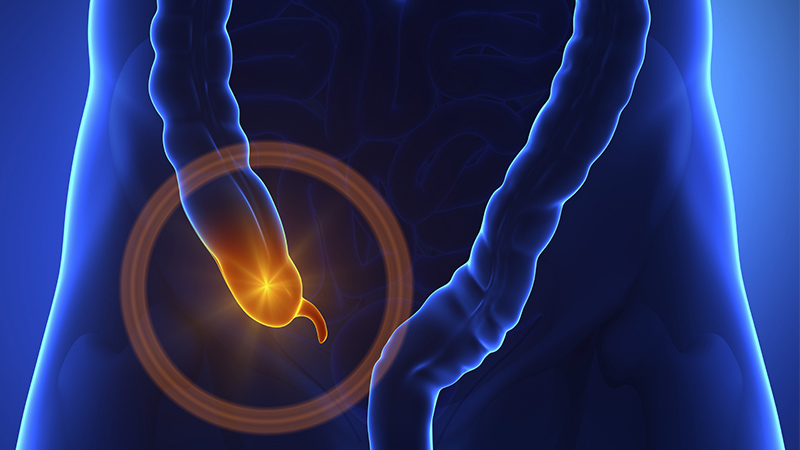

در واقع، آپاندیس به عنوان یک ساختار کیسهای شکل، از سکوم (کور روده) که ابتدای روده بزرگ است، بیرون میآید و به دلیل اهمیت آن در برخی از عملکردهای رودهای، مورد توجه قرار گرفته است.

یکی از مزایای بالقوه جهانی بدون آپاندیس میتواند کاهش موارد آپاندیسیت باشد. برآوردها نشان میدهد که در سطح جهانی هر سال بیش از ده میلیون مورد آپاندیسیت گزارش میشود و تا 50 هزار نفر جان خود را به سبب آن از دست میدهند.

برداشت آپاندیس از طریق جراحی، به عنوان یکی از عمومیترین جراحیهای شکمی شناخته میشود. در صورت عدم وجود آپاندیس، افراد دیگر به علت آپاندیسیت جان خود را از دست نمیدادند و هزینههای مرتبط با جراحی و بستری نیز وجود نداشت.

به گفتهی پارکر، تحقیقات پیشین نشان دادهاند که آپاندیسیت ممکن است ناشی از تغییرات فرهنگی و بهداشتی مرتبط با جامعه صنعتی باشد.